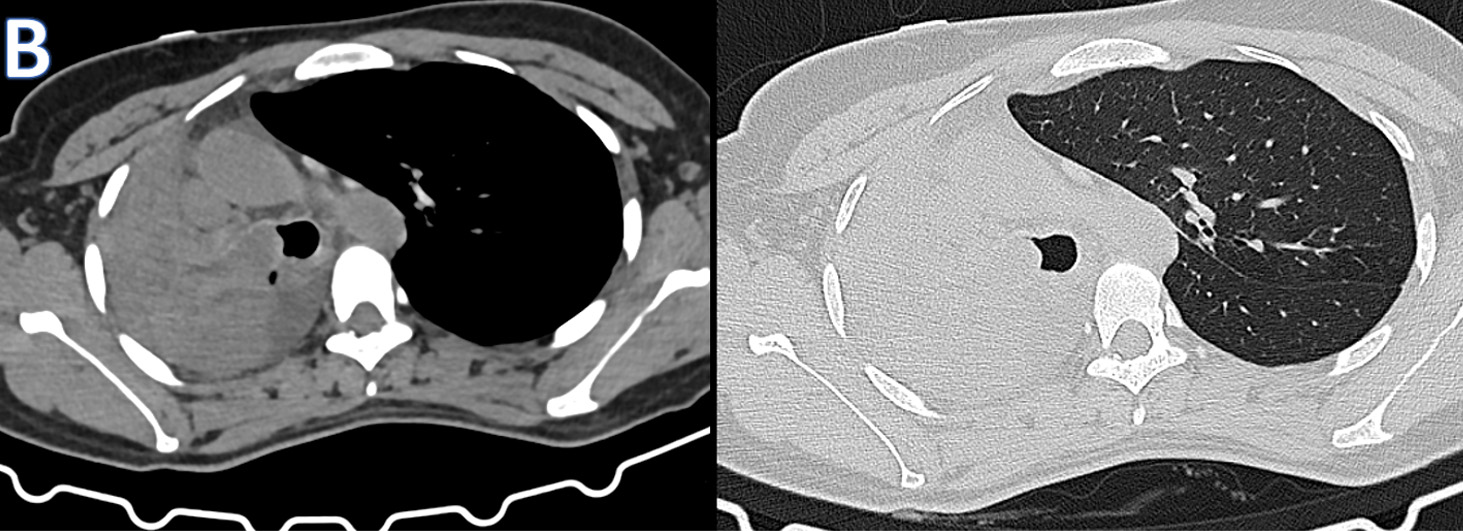

C – CORONAL CT THORAX

Ovoid heterogeneously isodense mass lesion with multiple tiny peripheral specks of calcifications in the right hemithorax with endobronchial extension.